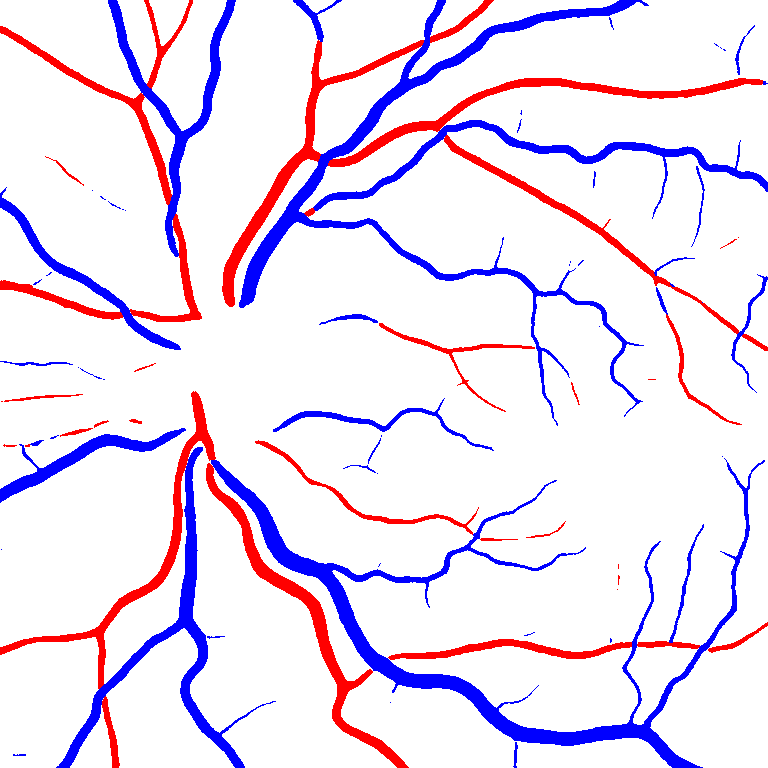

As reported in Table IV, we compared the SegRAVIR model against competing deep learning-based segmentation approaches on the RAVIR dataset. Evidently, SegRAVIR outperforms these methods as judged by all metrics for artery and vein classes with a healthy margin. In terms of Dice score, SegRAVIR outperforms CE-NET, IterNet and AG-Net by , and for artery segmentation and by , and for vein segmentation, respectively. Fig. 4 presents a qualitative comparison of the semantic segmentation outputs of SegRAVIR, CE-Net, and U-Net. Specifically, SegRAVIR yields more accurate vessel topology (i.e., thickness and orientation) segmentation with higher pixel-wise classification accuracy.

Table V presents quantitative performance benchmarks of SegRAVIR and other competing approaches for retinal artery and vein classification on the RITE dataset [11]. SegRAVIR outperforms previous state-of-the-art approaches in terms of accuracy, sensitivity, and specificity. Fig. 5 provides a qualitative comparison between segmentation outputs of SegRAVIR and the method of Hemelings et al. [40] on the RITE test set.